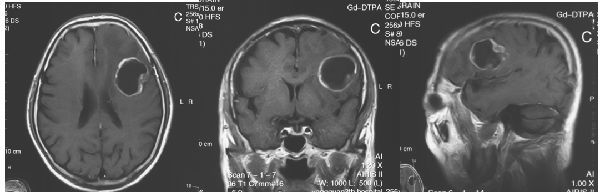

患者为老年男性,因“头痛伴言语不清2周”入院。神经功能障碍主要表现为运动性失语。术前头颅MRI提示:左侧额下回运动性语言功能区的囊性占位,呈环形强化,周边有广泛水肿,左侧侧脑室轻度受压。